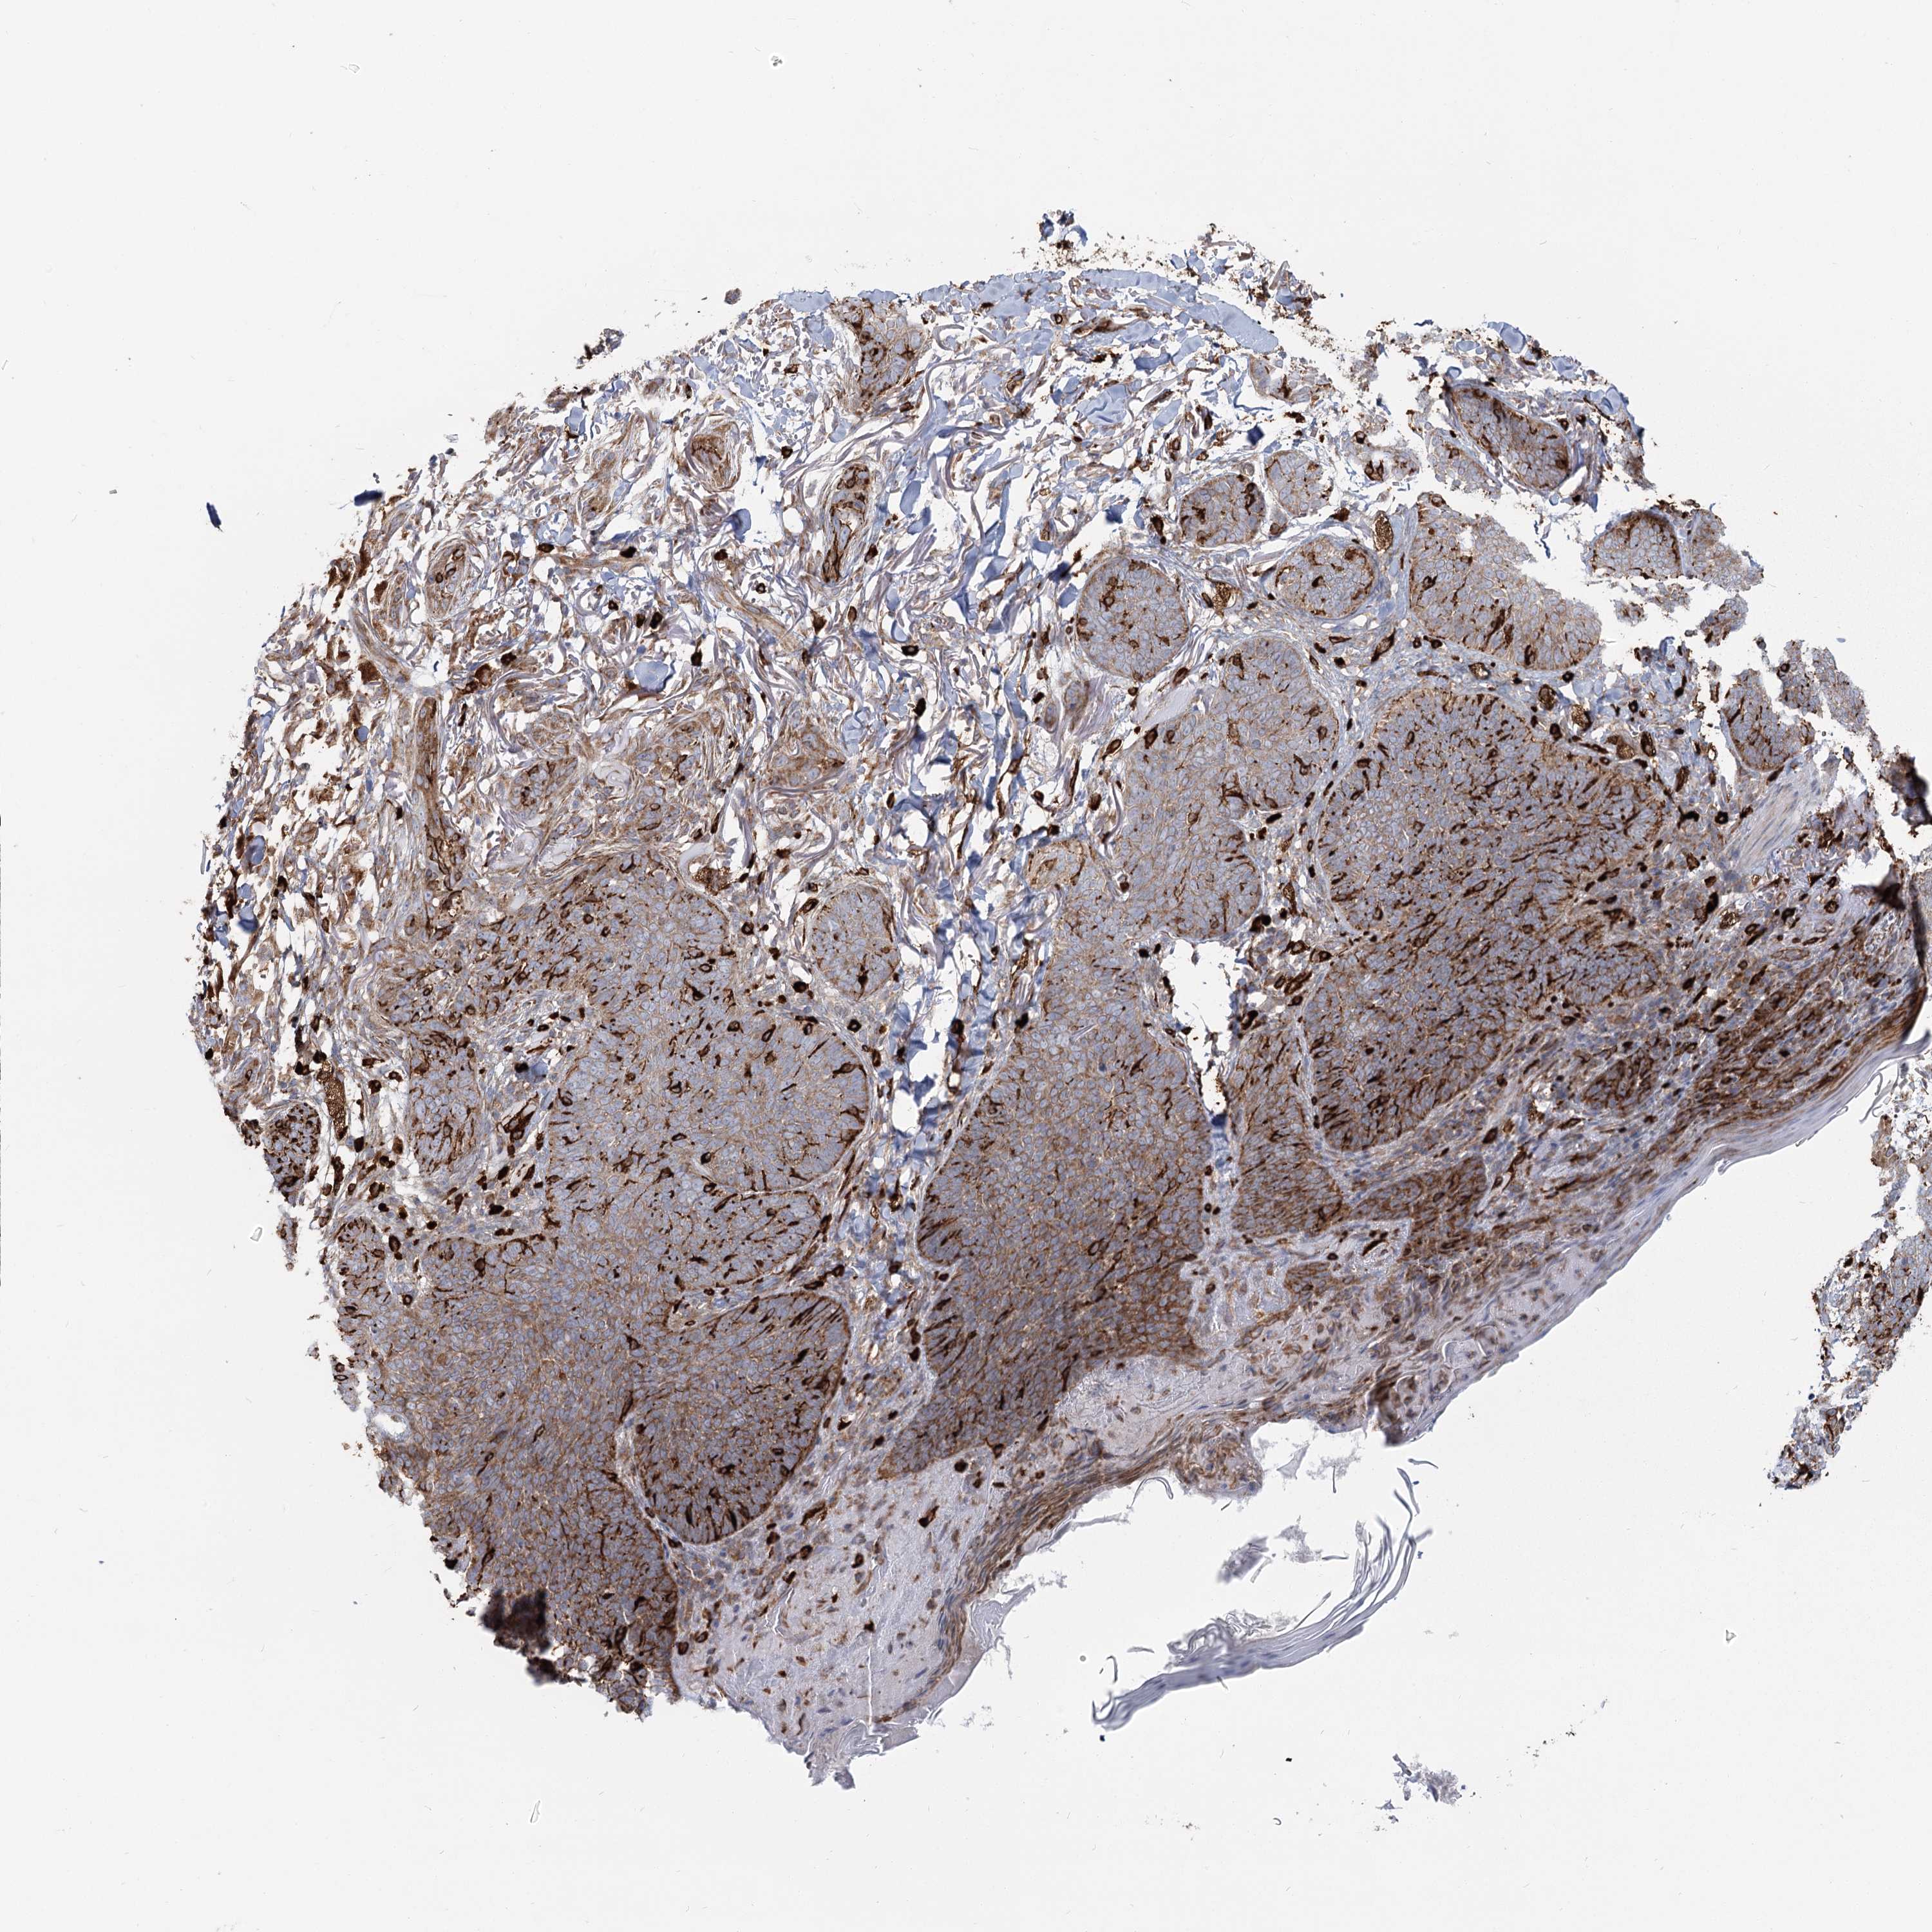

Basal cell and squamous cell cancer

SKIN CANCER - Protein expressioni

A mouse-over function shows sample information and annotation data. Click on an image to view it in a full screen mode. Samples can be filtered based on level of antibody staining by selecting one or several of the following categories: high, medium, low and not detected. The assay and annotation is described here.

Antibody stainingi

Antibody staining in the annotated cell types in the current human tissue is reported as not detected, low, medium, or high, based on conventional immunohistochemistry profiling in selected tissues. This score is based on the combination of the staining intensity and fraction of stained cells.

Each image is clickable and will lead to virtual microscopy that enables deeper exploration of all samples and also displays staining intensity scores, fraction scores and subcellular localization as well as patient and tissue information for each sample.

Antibody HPA035941

Squamous cell carcinoma, NOS